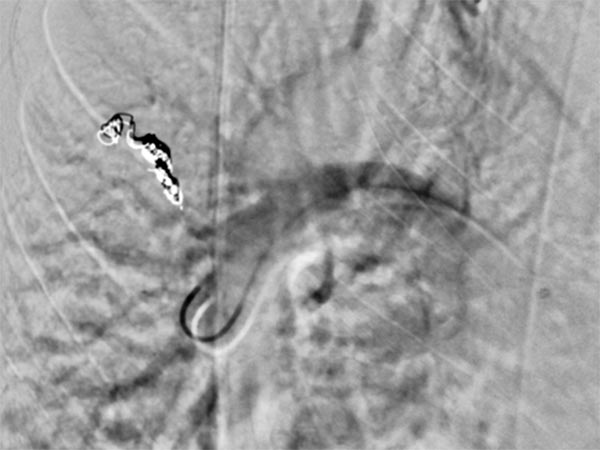

The feeding arteries are occluded with several coils. Parts of the coils are placed in the arterial feeding branch for secure anchoring (anchor technique). The pulmonary AVM is occluded. In the former aneurysm there is still some contrast medium stasis from a previous injection.

Completion DSA via the pulmonary trunk shows no more flow into the pulmonary AVMs.